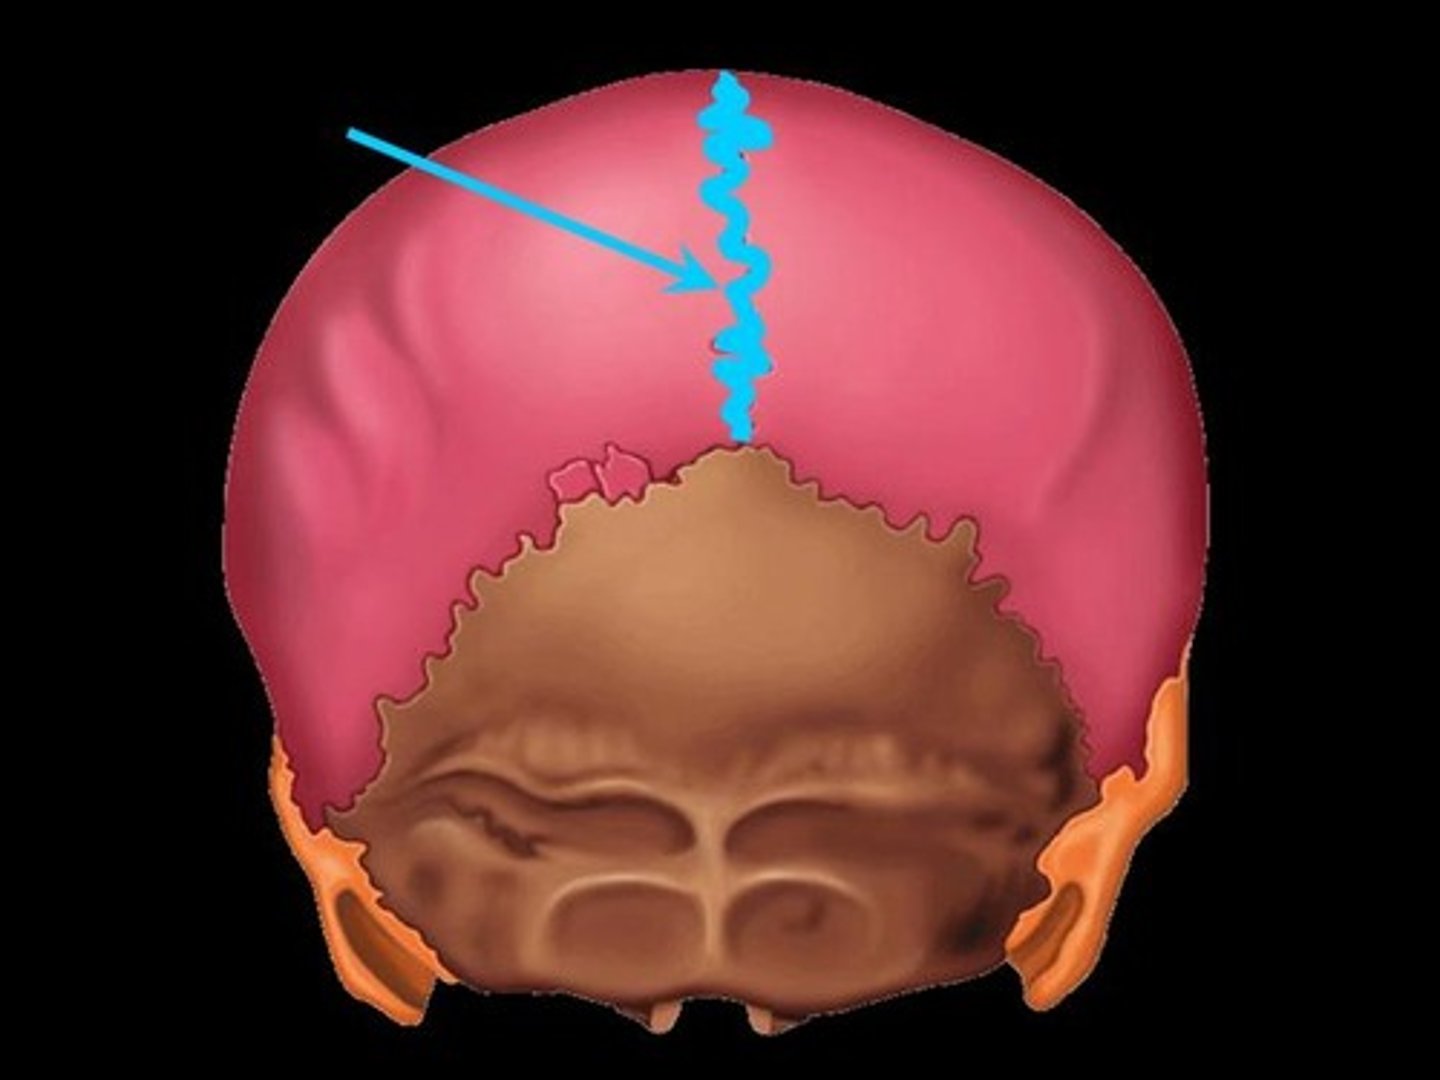

sagittal suture

bregma

lambda

parietal bone

occipital bone